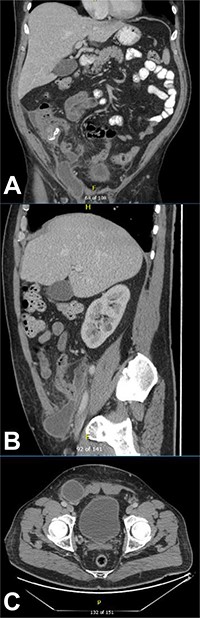

CT of the abdomen and pelvis demonstrating a reduction in size of the fluid collection/abscess in the inguinal hernia sac in (A) coronal (B) sagittal and (C) apical planes.

This collection was drained under ultrasound guidance, and a pigtail catheter was left in situ for 1 week. The patient progressively recovered. A repeat CT of the abdomen and pelvis after a week demonstrated a reduction of the collection (Fig. 3).